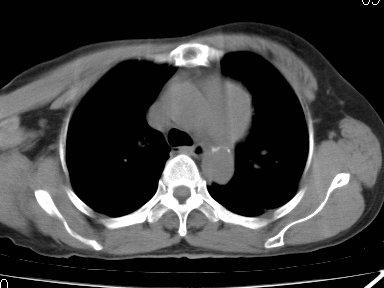

ct4228158f胸片示主动脉弓增宽主动脉瘤未排除纵

看片诊病之典型急诊胸片分享

冯xx男51岁五官科诊咽炎,咳嗽行胸片常规检查,发现右下肺占位,ct同诊